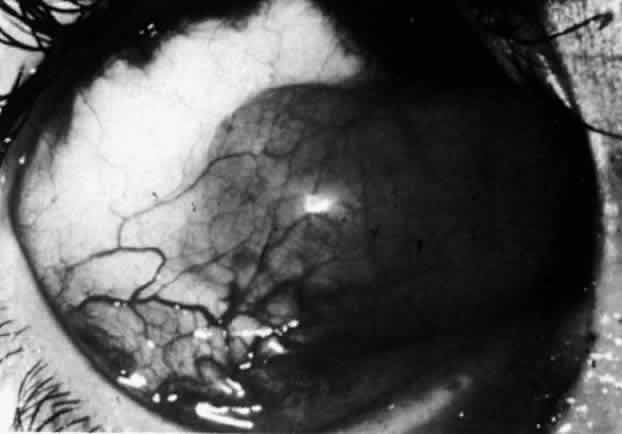

The redness of simple episcleritis may be intense, varying from a fiery-red or a brick-red discoloration to a mild red flush, but it does not have the bluish tinge that is seen in scleritis. The distribution is usually sectorial but can involve the whole anterior segment of the globe. The episcleral vessels are engorged but retain their normal radial position and architecture (Figs. 13 and 14; Color Plate 1A). In simple episcleritis, there is a diffuse edema of the episcleral tissues. These tissues are sometimes infiltrated with gray deposits that appear yellow in red-free light. Surprisingly, the eye is rarely tender to the touch.

Diffuse Anterior Scleritis Diffuse anterior scleritis is the most common and least severe type of scleritis. The inflammation is widespread, and it may involve either a small segment or the whole of the anterior segment, sometimes with such severe overlying inflammation as to justify the name “brawny” scleritis (Fig. 29). On slit lamp examination, the vascular pattern of both deep and superficial layers may be distorted, so that the normal radial pattern of the vessels is lost; large anastomotic channels develop, leading to beading and tortuosity of the remaining vessels (Figs. 30 and 31; Color Plate 1C).